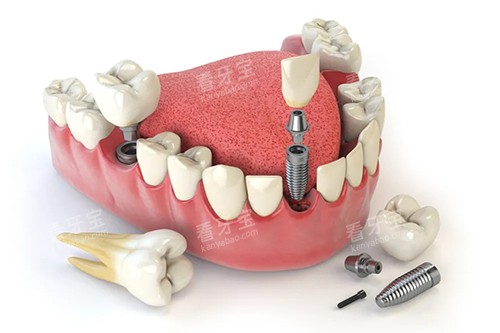

为了给患者提供更更准一些、较高的效率的治疗,贵阳龅牙兔口腔引进了一系列靠前的口腔医疗设备。

例如,智能化口腔全景机能够快速、比较准地拍摄口腔全景片,帮助医生齐全了解患者口腔的整体情况;口腔CT设备则可以提供更详细的三维影像,为种植牙等复杂手术提供精细的诊断依据。

靠前的设备不仅提高了诊断的比较准性,还缩短了治疗时间,减少了患者的痛苦。